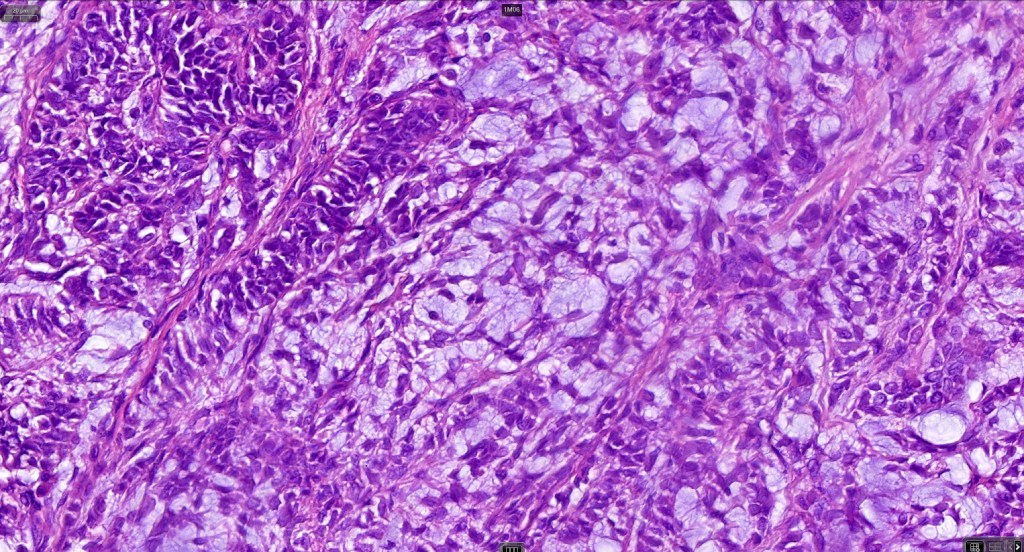

Histological features

•Pure population of myoepithelial cells dispersed in sheet-like, reticular, whorled or fascicular patterns in a myxoid or hyaline stroma

•Cell types include epithelioid, spindled, histiocytoid & plasmacytoid

•Syncytial myoepithelioma characterized by sheet-like growth of ovoid to spindle cells with pale cytoplasm, syncytial borders & vesicular nuclei

•In malignant myoepithelioma there is an infiltrating border, marked pleomorphism, high mitotic rate & necrosis. Perineural infiltration & lymphovascular invasion may be seen